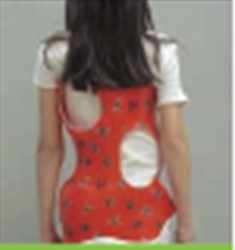

Skoliosetherapie (Chêneau-Korsett, operative Behandlung)

Das Chêneau-Korsett wird bei Patienten angewendet, die sich im Wachstumsalter befinden und an einer progredienten idiopathischen Skoliose leiden. Das Chêneau-Korsett ist asymmetrisch gebaut und bildet neben Druckzonen (Pelotten) auch Freiräume (Expansionszonen).

Beim Bau des Korsetts wird zunächst ein Gipsabdruck angefertigt. Daraus erstellt der Orthopädie-Mechaniker das Korsett mit drei Druckpunkten, um einen aktiven Ausgleich der Fehlhaltung zu erwirken. Wichtig ist eine gleichzeitige muskuläre Stabilisierung der Wirbelsäule, so dass wir unsere Patienten zu einer regelmäßigen sportlichen Betätigung ermutigen. Eine operative Korrektur ist nur bei einer geringen Zahl der Skoliosepatienten notwendig.